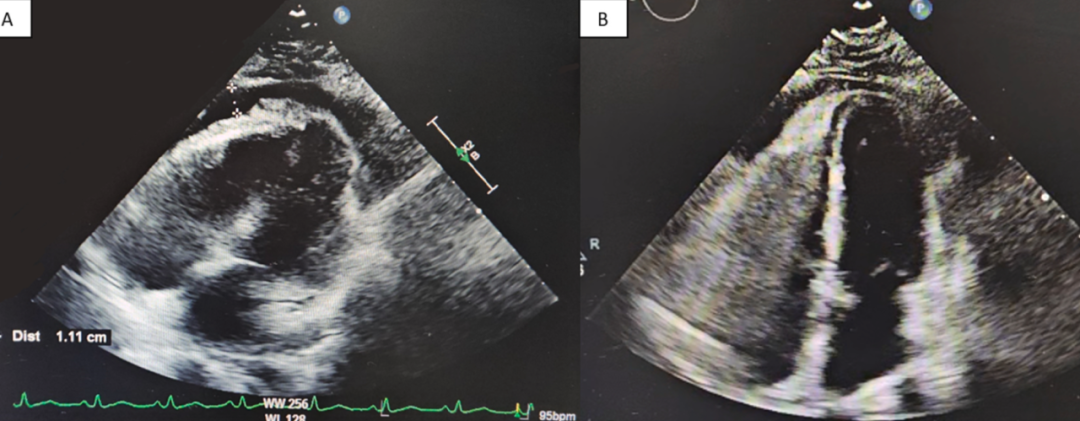

经胸超声心动图(TTE)示左心室轻度向心性肥厚, LVEF为65-70%,少量至中量心包积液,无心包填塞征象(图3A)。血清病毒学PCR检测甲型流感阳性(亚型可能为H2N2、H5N3或H10N7),但H1、H1N1/pdm09及H3亚型呈阴性。IgG抗体检测显示巨细胞病毒、EB病毒及细小病毒B19阳性,但这些病毒的IgM抗体呈阴性,提示既往感染。

图3 经胸超声心动图,治疗前和2天后

患者立即接受奥司他韦75 mg每日两次(共5天)、秋水仙碱0.6 mg每日两次(共30天)及布洛芬600 mg每日三次(共5天)治疗。出院前复查TTE显示心包积液显著减少(图3B)。患者临床症状逐步改善。